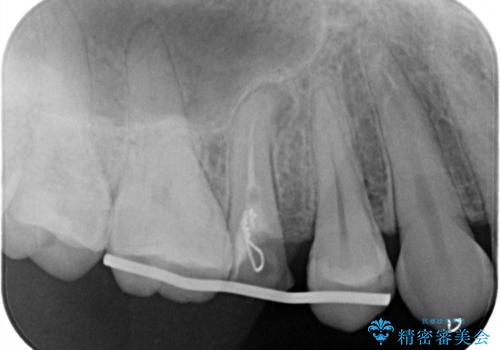

右上の被せものを除去したところ、中で歯が割れていたため、部分矯正で引っ張り出すことになりました。

歯を引っ張り出したり、歯肉の手術の経過待ちの間に、患者様のご希望で他の歯の虫歯治療も行いました。

・基本的には失活歯(根管治療済の歯)が対象となります。

・約3か月ほど引っ張り出します。

・両どなりの歯に一時的にワイヤーを接着します。

・十分に引っ張り出した後、歯肉の手術が必要となります。

・歯肉が落ち着いてから最終的な被せものの製作となります(約3か月)。

・歯の割れ方によっては引っ張り出す対象外となります(抜歯になります)。